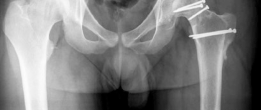

Fixation is achieved using multiple countersunk headless compression screws or bioabsorbable pins. The trajectory of the screws must be meticulously planned to cross the osteotomy site perpendicularly, maximizing interfragmentary compression while avoiding penetration into the articular surface or the vital posterior retinacular vessels. Fluoroscopy is utilized to confirm anatomic reduction, appropriate screw length, and the absence of intra-articular hardware.

The hip is then reduced back into the acetabulum. The joint is taken through a full range of motion to confirm the resolution of hinge abduction and the restoration of impingement-free kinematics. The capsule is closed loosely to prevent postoperative intra-articular hypertension. The trochanteric flip osteotomy is reduced and fixed using two or three 4.5 millimeter cortical screws.